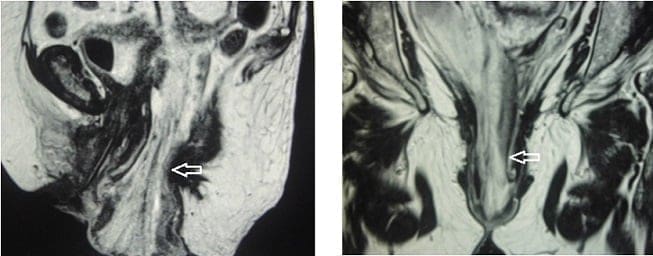

Se inició nutrición parenteral total cinco días después y se solicitó una resonancia magnética abdominopélvica que reveló introito vaginal ampliado de 5 cm de diámetro anteroposterior, el cual estaba ocupado en su interior por asas intestinales y mesenterio protruido (Figura 3).

Figura 3. Resonancia magnética de la pelvis, donde se observa el introito vaginal ampliado,

de 5 cm de diámetro, por donde protruyen las asas intestinales y el mesenterio (flechas).

Fuente: original de los autores.